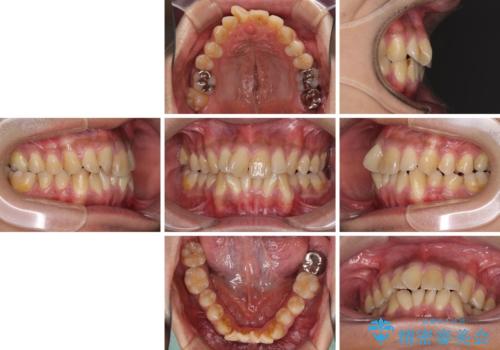

上顎の狭い歯列をインビザラインで拡大

- 上下前歯の叢生を気にして来院された患者様です。

奥歯はクロスバイトとなっているので上顎は側方拡大を行いつつ、上下全体の叢生をインビザラインにより改善することとしました。

治療途中でクリーニングやホワイトニングを行い、歯列が整うと同時に明るい口元となりました。